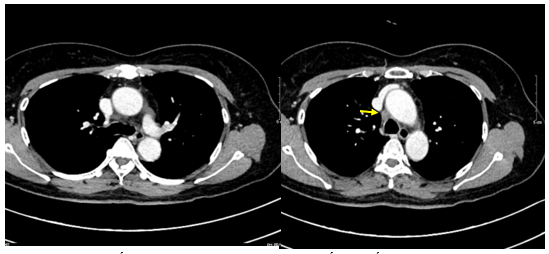

- Chụp cắt lớp vi tính lồng ngực: Nhu mô thùy trên phổi (Phải) có nốt tổn thương kích thước 13x14mm,bờ không đều, ngấm thuốc, sau tiêm. Rải rác nốt đặc 2 bên thùy phổi kích thước 3-10mm. Trung thất các nhóm 1R; 2R; 4R; 5; 8; 10RL có vài hạch lớn nhất kích thước 26x15mm; bờ không đều; ngấm thuốc không đồng nhất sau tiêm. Thượng đòn 2 bên có vài hạch tính chất tương tự; hạch bên phải kích thước 11x14mm

Hình 1.

Hình ảnh cắt lớp vi tính ngực có tiêm: thùy trên phổi (P) có nốt tổn thương kích thước 13x14mm, bờ không đều, ngấm thuốc, sau tiêm. Nghi ngờ tổn thương nguyên phát (mũi tên đỏ)

Hình 2: Hình ảnh cắt lớp vi tính ngực có tiêm: Rải rác nốt đặc 2 bên thùy phổi kích thước 3-10mm (các mũi tên màu xanh lá)